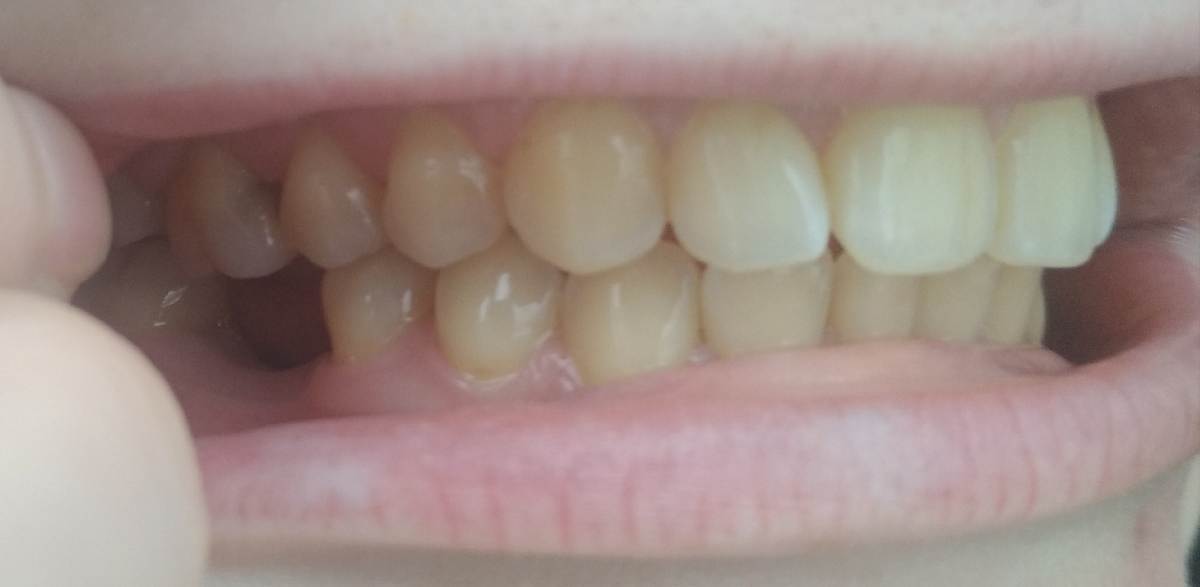

Здравствуйте, подскажите, целесообразно и нужно ли в моем случае ортодонтическое лечение? После лечения зубов планирую установку имплантов в области 36 и 46 зубов. Нужно ли что-то исправлять, или в моем случае можно поставить импланты как есть, без негативных последствий со стороны прикуса? Ортопед на консультации сказал, что можно, по поводу прикуса ничего сказано не было. Была у 2 ортодонтов: первый сказал, что прикус глубокий, и нужно исправлять брекетами. Второй сказал, что небольшие нарушения есть, но как я поняла, не сильно критичные (в области верхних резцов, боковых зубов на верхней челюсти, поэтому наблюдается оголение десны из того, что запомнила), и рекомендовал лечение элайнерами. Жалоб нет, кроме бруксизма (врачи сказали, что причина не в прикусе) и смущает выдвинувшийся 16 зуб. Этот панорамный снимок выдали после КТ, КТ также есть на диске. Спасибо.